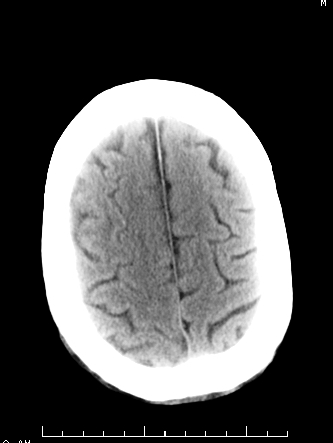

m/50,头昏头痛1月,近3天感觉左半肢体活动不利,自述半年前呈患肺tb,腰穿脑脊液未见特殊改变。现做头颅ct请大家会诊。

考虑:1.结核脓肿,2.星形胶质瘤,但脑积液正常,这考虑肿瘤的可能性大些.期待结果

首先考虑肿瘤性病变,星形细胞瘤可能性大,不排外转移瘤。建议mri。

感染性病变;脑干脓肿(脓肿壁形成期),基底节及内囊(脑炎期)。顺便问一句,该病人是不是抵抗力很差,有没有糖尿病。

请大家结合临床表现看一下 左侧肢体的症状是脑干 还是其他的问题 另外结核感染脑脊液应该有问题 所以应该考虑肿瘤性病变